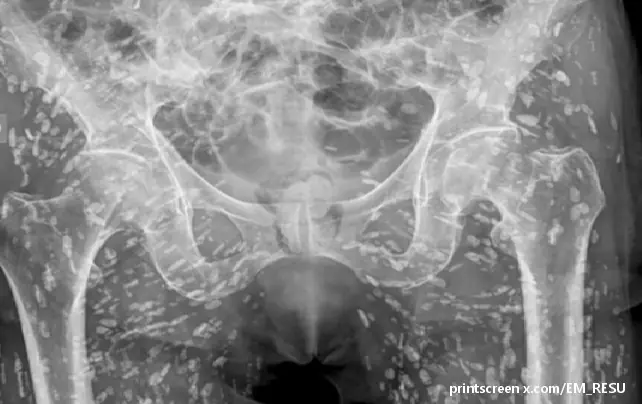

Sem Gali, lekar hitne pomoći specijalizovan za kardiovaskularne hitne slučajeve i hitnu radiologiju, nedavno je podelio neobičan rendgenski snimak pacijentovog karličnog područja koji je pokazao njegovo telo izrešetano stotinama belih tačaka.

Sve su to bila kalcifikovana jajašca trakavice koja su se zaglavila u mekim tkivima njegovog donjeg dela tela.

„Ovo je stanje poznato kao cisticerkoza, u suštini to su ciste larve taenia soliuma, takođe poznate kao svinjska trakavica“, rekao je Gali na društvenoj mreži X (Tvitter).

„Ove ciste mogu da putuju bilo gde po celom telu, u velikoj meri do mišićnog i mekog tkiva kukova i nogu.“

Osim ako ne stignu do mozga, ova kalcifikovana jaja su u osnovi bezopasna, više nisu održiva, ali ako je sama pomisao da su zaražene stotinama ovih cista nalik na pirinčano zrno nedokučiva, želećete da se klonite sirovih ili nedovoljno kuvanih svinjetinu i ribu, samo da budemo sigurni.